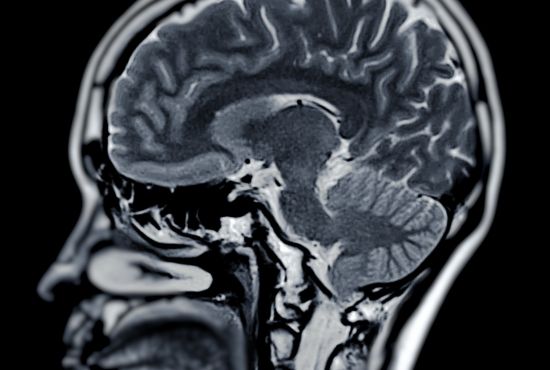

Le dos est une structure complexe, constituée de 33 vertèbres (cervicales, thoraciques, lombaires, sacrées et coccygiennes), de disques intervertébraux, de ligaments, de muscles dorsaux, et de la moelle épinière qui véhicule les informations nerveuses du système nerveux central vers les membres inférieurs. Voici les pathologies les plus fréquentes :

L’IRM est particulièrement utile pour visualiser les disques intervertébraux, la moelle épinière, les nerfs et détecter une éventuelle hernie ou compression. Le scanner permet de repérer une fracture vertébrale, un bombement discal ou une sténose. La radiographie est indiquée pour observer les structures osseuses et les déformations comme la scoliose ou la cyphose.